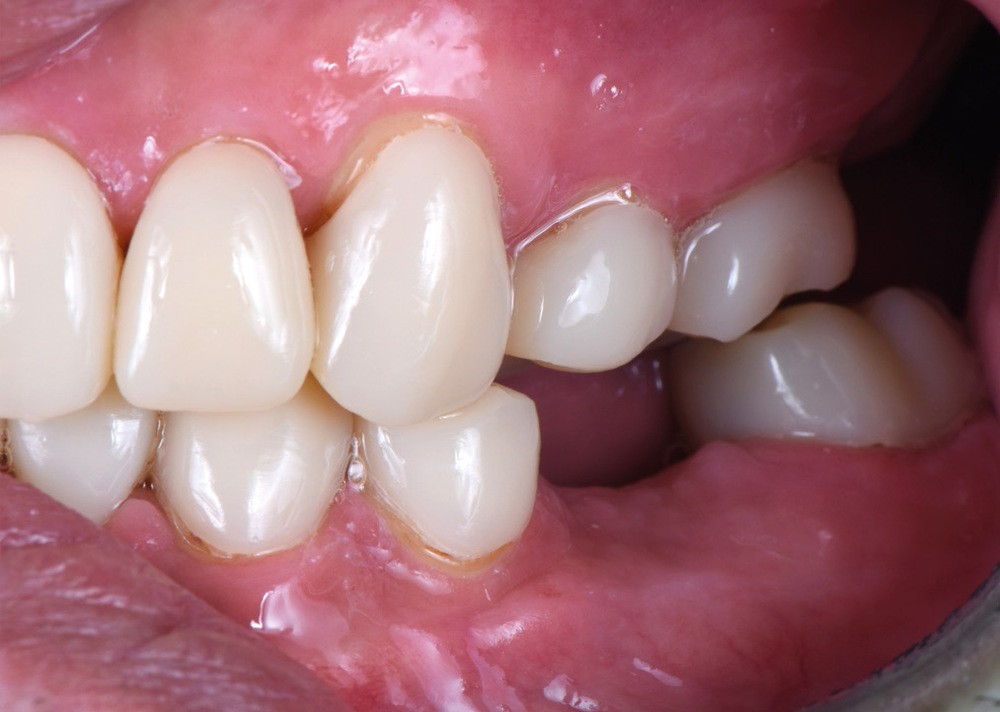

Au vu du contexte para-fonctionnel et de l’étendue de la perte tissulaire, des coiffes périphériques minimalement invasives ont été choisies afin de restaurer l’esthétique et la fonction. Actuellement, aucun consensus n’est fait sur le choix du matériau d’infrastructure à privilégier. Les matériaux hybrides usinables présentent des propriétés mécaniques, physiques et biologiques intéressantes en contexte d’usure sévère (e.g., module d’élasticité, résistance à la propagation de fêlures, facilité de réintervention). Une réhabilitation globale avec remontée de dimension verticale d’occlusion (DVO) par l’intermédiaire de coiffes composites renforcés en nano-céramiques est décrite.